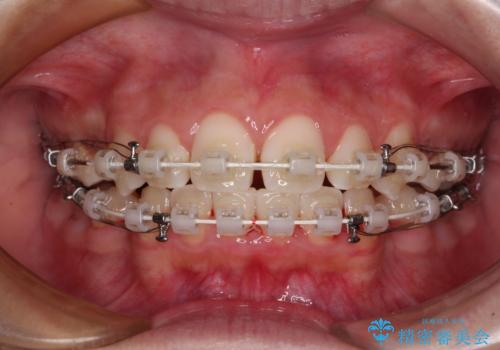

- 矯正装置

- 審美装置

- 口元の突出感で口が閉じにくいとのことで来院された患者様です。

上下左右の第一小臼歯4本を抜歯し、ワイヤー装置での抜歯矯正を行うこととしました。

右側の咬み合わせは、上顎がやや前方位にある状態であったので、通常は補助装置を併用するのですが、高校生ということで補助装置なしで治療を行うこととしました。